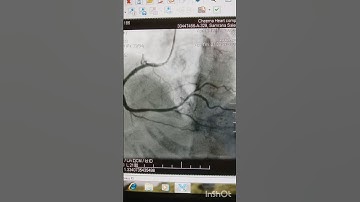

EBC 2025 - SESSION 15 - News in LM PCI